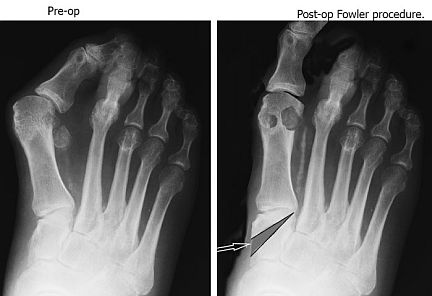

One of more reliable procedures I’ve done over the years is the Fowler. Rarely mentioned and one of the more powerful procedures I’ve had in my armamentarium of proximal procedures. The Fowler has the advantage of preserving the function of the 1st met/medial cuneiform joint (if normal), correcting the congruence of the joint if it is angled, improving the deformity, and can be used to predictably lengthen the 1st ray.

Fowler Precedure |

In Dr. Morrelli ’s case, the IM is good, but the 1st met/medial cuneiform is angled, and the 1st ray is short compared to the 2nd metatarsal. All of these things could be adequately addressed (IM, 1st met/medial cuneiform angle and length) by the Fowler. In the past, I’ve corrected up to a 45° IM angle (when 4 other surgeons in town told the patient, “nothing could be done”). I like to use a femoral head graft with Symphony with a mesh plate from Osteomed's ocular trauma set with self-drilling and self-tapping screws. This will allow limited weight-bearing after a week and full weight-bearing after four weeks.